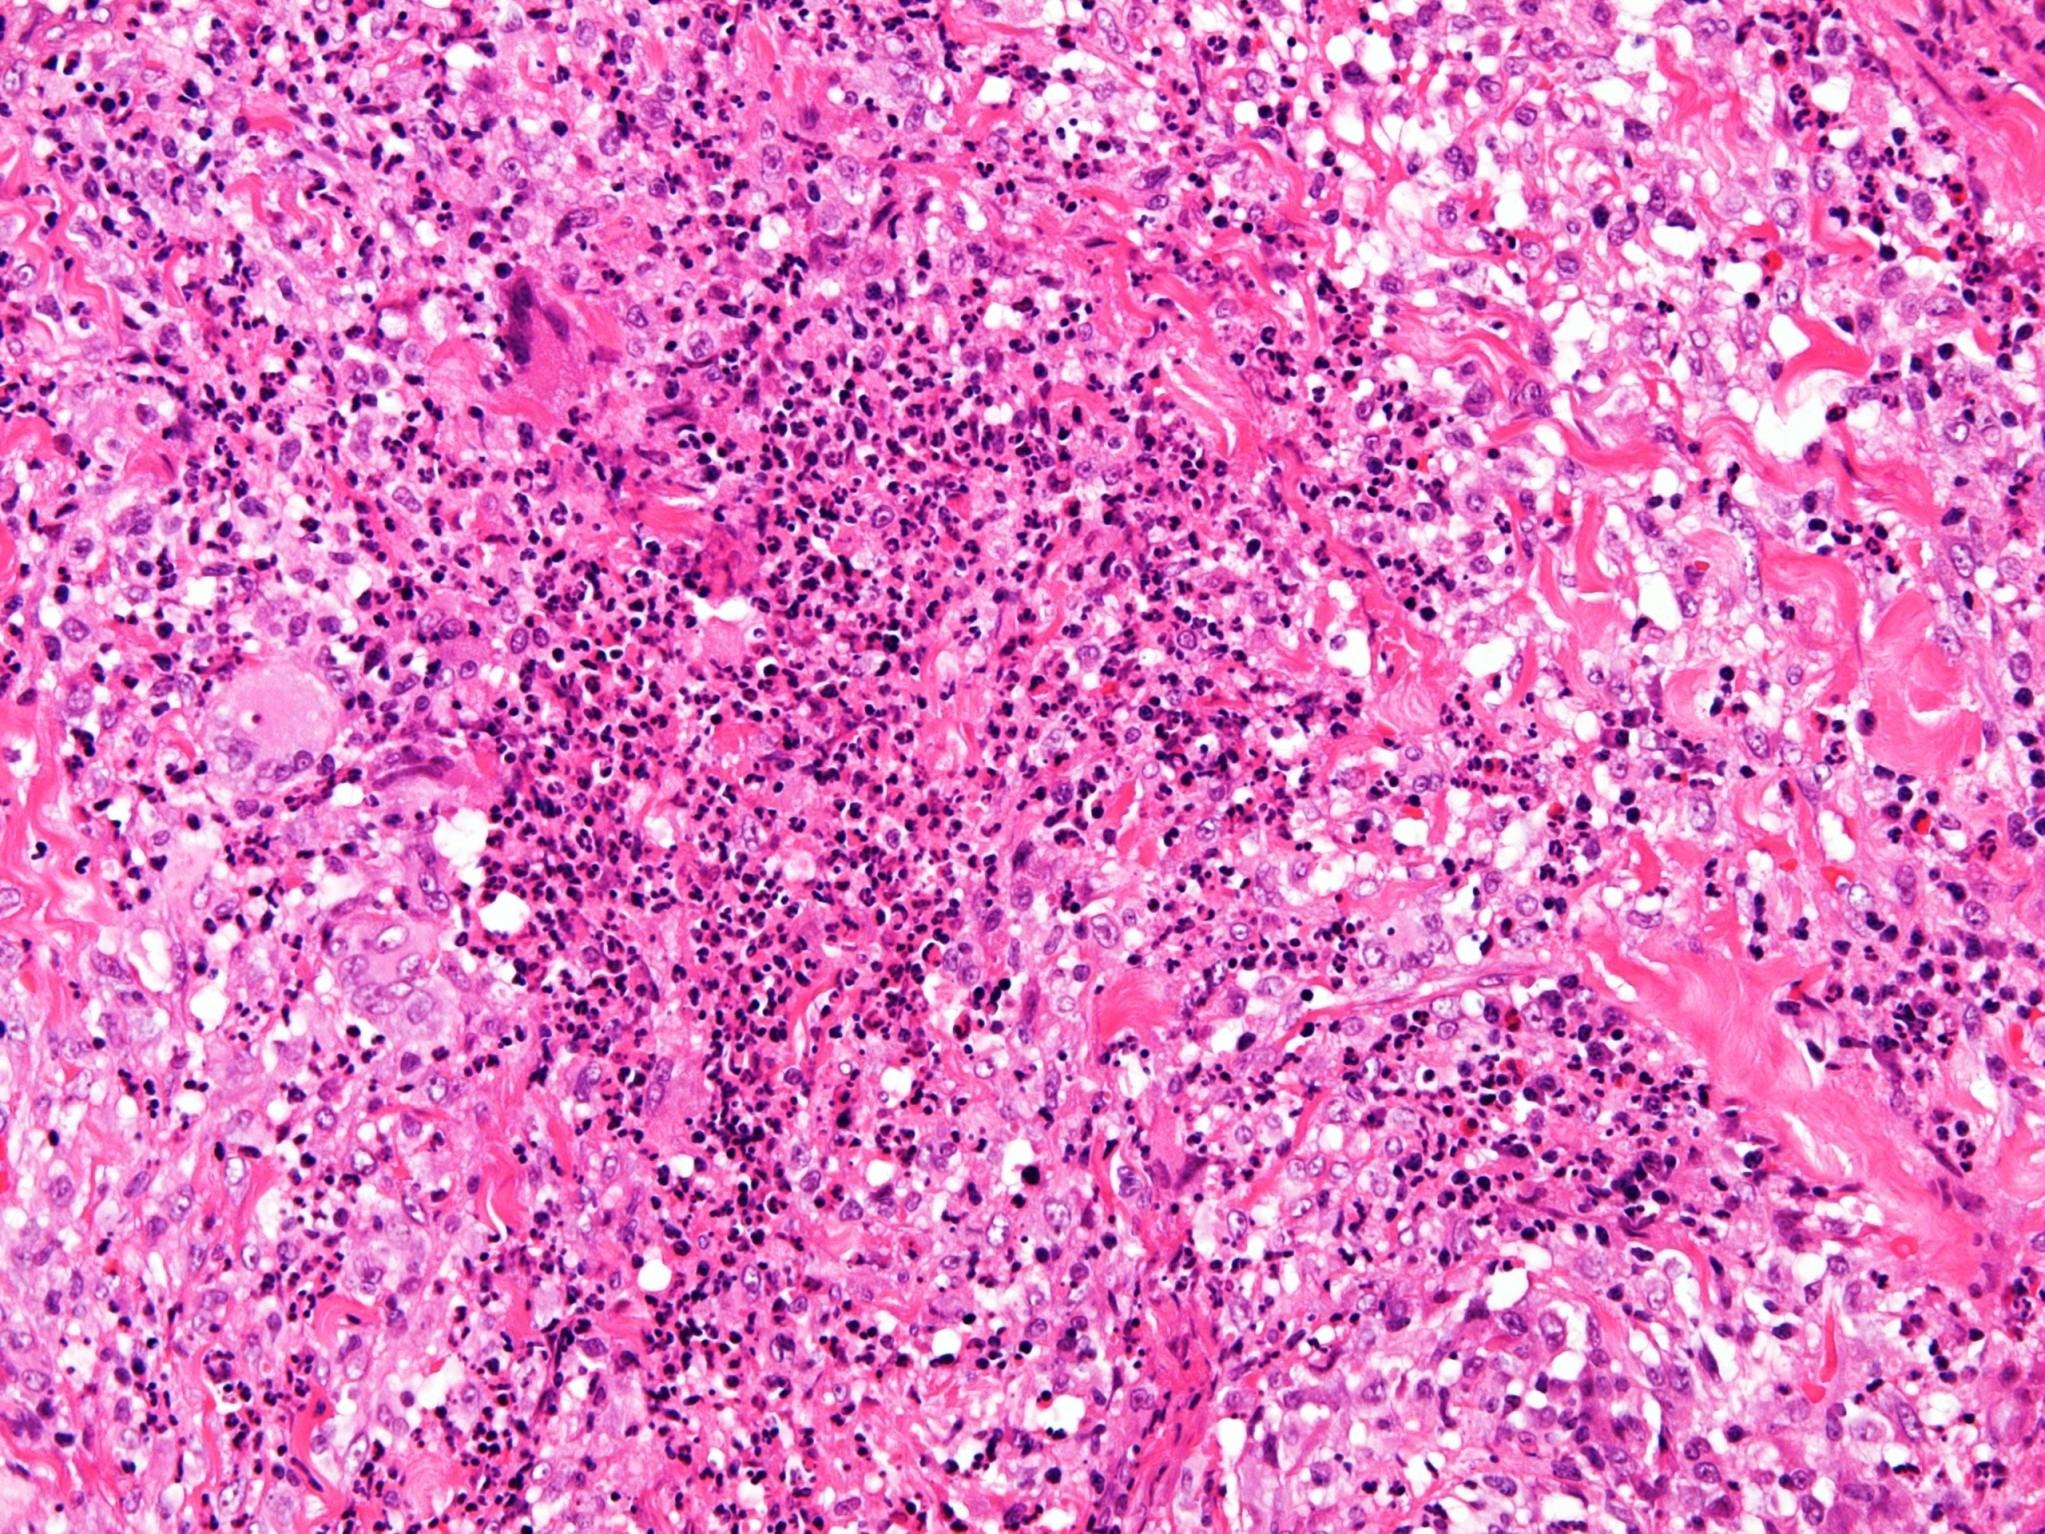

Sinonasal NK/T cell lymphoma

 Broad morphological spectrum

 Polymorphic with atypical lymphoid cells

 Plus background of other cells (neuts eos)

 Pale to clear cytoplasm

 Angioinvasion

 Geographic necrosis

 CD56, variable for T cell markers (CD2)

 EBV related

a, Proliferation of small to large, pleomorphic lymphoma cells

b, Lymphoma cells are invading a vein (arrows)